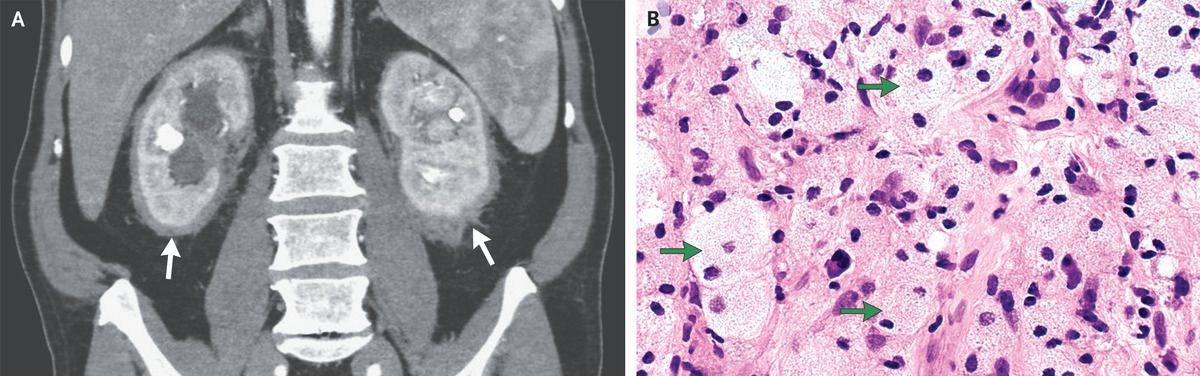

A 62-year-old man undergoing abdominal ultrasonography for the evaluation of gallstones was found to have a retroperitoneal mass. A physical examination and the results of routine laboratory studies, including tests of renal function, were normal. A computed tomographic (CT) urogram showed soft-tissue infiltration of the kidneys (Panel A, arrows), severe hydronephrosis of both kidneys, and moderate splenomegaly. Subsequent positron-emission tomography–CT showed no hypermetabolic activity. Stents were placed in both ureters, and a core-biopsy specimen of the perinephric soft tissue was obtained. Histopathological examination of the specimen revealed diffuse infiltration with pale-staining histiocytes (Panel B, arrows; hematoxylin and eosin staining) admixed with scattered lymphocytes and plasma cells. Immunostaining showed that the cells were strongly positive for CD68 and negative for S100 and CD1a. Molecular testing detected a BRAF V600E mutation. A diagnosis of Erdheim–Chester disease was made. Erdheim–Chester disease is a non–Langerhans-cell histiocytosis that is typically manifested by sclerotic lesions in the long bones — a feature that this patient uniquely did not have. This disease is also associated with numerous extraosseous findings, including infiltration of the retroperitoneal perinephric tissue, which results in a “hairy kidney” appearance on cross-sectional imaging, as was seen in this patient. Treatment with vemurafenib, a targeted inhibitor of the mutated BRAF V600E kinase, was started. At a 1-year follow-up visit, the patient had had no disease progression.